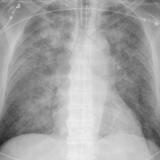

APE 5

Date: 11/05/2005

Views: 2662

APE 6

+ IABP

Date: 01/13/2008

Views: 3390